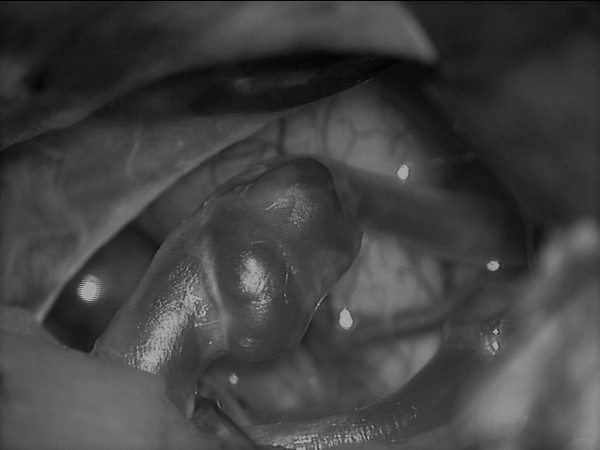

또 한가지 큰 변화와 발전 중 하나는 혈관내 색전술이라는 새로운 치료법의 등장이다. 1990년대에 처음 등장한 코일 색전술은 풍선처럼 부풀어 오른 뇌동맥류 주머니 안에 매우 가느다란 코일을 채워 넣어서 파열을 방지하는 치료법이다. 2000년 초반 뇌지주막하출혈의 국제 다기관 공동임상연구(International Subarachnoid Trial)에서 기존의 수술적 클립 결찰술보다 효용성이 우월한 것으로 인정되는 결과를 보이면서 뇌동맥류 치료 패러다임의 대전환을 겪게 됐다. 이후 혈관내 색전술은 치료 재료의 발전과 함께 크게 확산됐다. 국내에서도 뇌동맥류에 대한 클립 결찰술과 코일 색전술 시행 건수가 2012년을 기점으로 역전돼 코일 색전술이 뇌동맥류 치료의 주된 치료법으로 자리 잡았다.